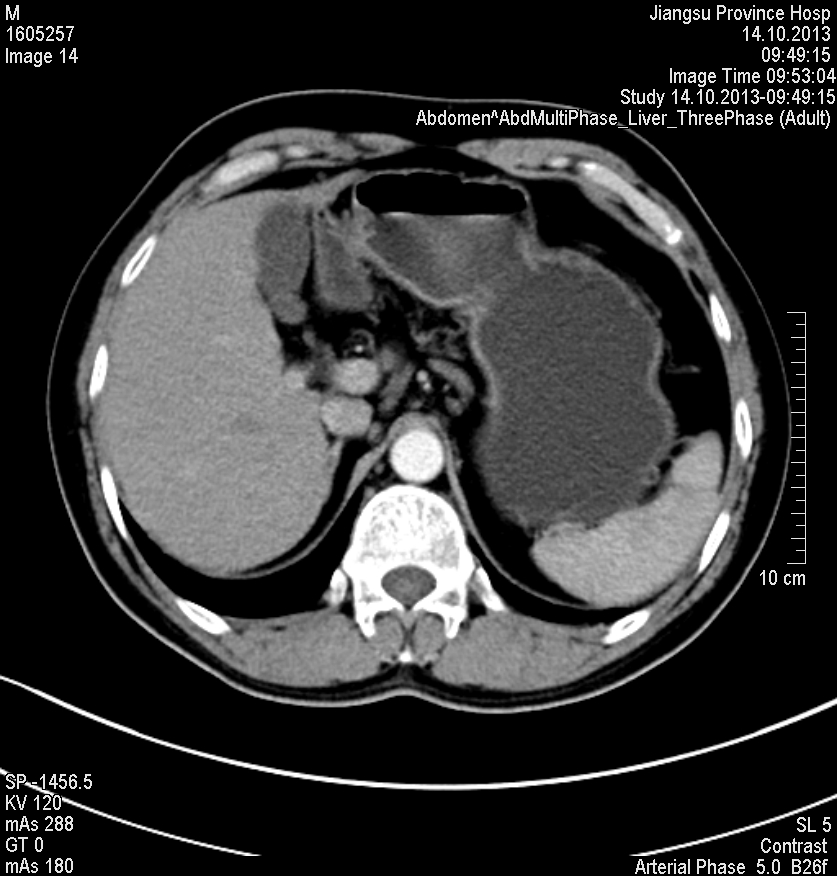

水成像高信号,同反相位均呈低信号,动脉早期轻度强化,其余时期强化不明显

肝脏右叶内有一明显圆形肿块,增强CT肝实质期不强化,MRI水成像高信号,其他呈低信号,动脉早期轻度强化。

感觉像小肝癌,强化方式快进快出